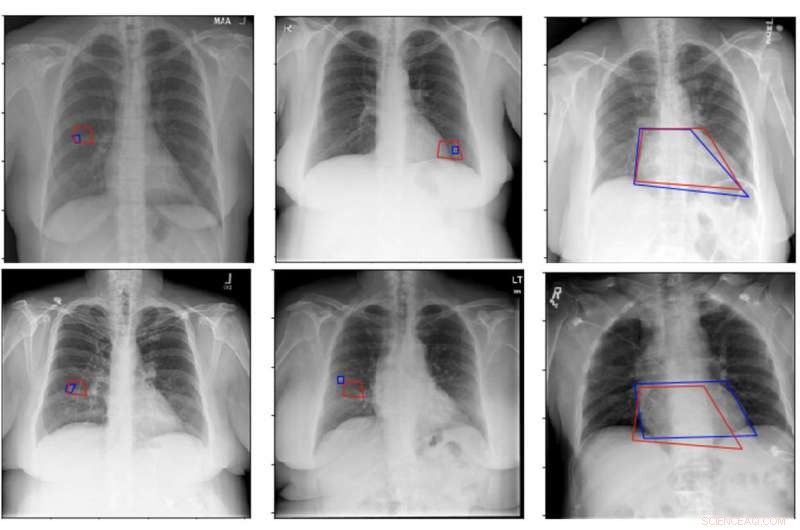

Sample results from a new network architecture show the estimated quadrilateral in red and the one marked by a radiologist in blue. The performance is a significant improvement over a previous architecture. Credit: IBM

Deep neural networks used to train AI systems can sometimes have difficulty breaking down medical images, a process called segmentation. This can present challenges to accurately identifying small disease markers, limiting the use of these networks in clinical settings. The project is our first effort directly targeting this challenge.

The researchers trained one network using combined image and text data and a second network using separated text and images, because there are different ways an AI-based imaging system might receive input to analyze. In the study, both networks autonomously located potential health threats in chest X-rays with a level of accuracy comparable to that of experienced radiologists analyzing and annotating the same images.